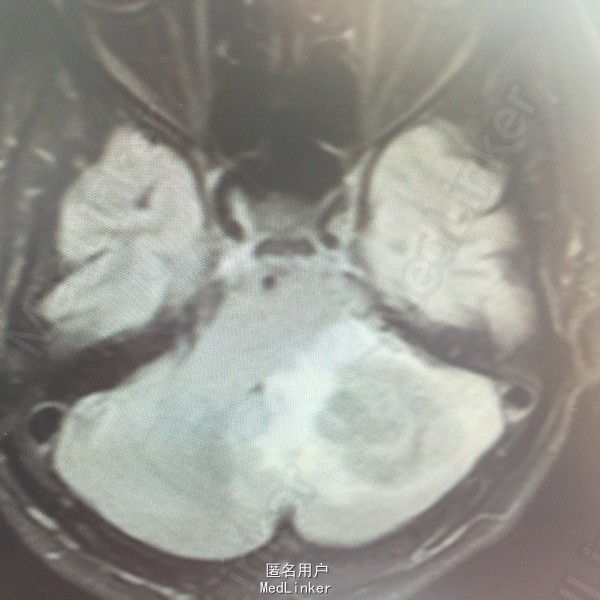

男,54岁,以头痛半个月入院。 现病史:半个月前无诱因头痛,呈胀痛,无呕吐,无意识障碍,病来咳嗽、咳痰,体重减轻约5斤,无发热。 既往史:无特殊。

查体:BP:150/100mmHg,神清语明,两瞳孔等大正圆,直径约3.0mm,光敏,四肢肌力5级,肌张力正常,腱反射艹,左侧共济运动阳性,病理征阳性,脑膜刺激征(-)。 辅查:见下:

肺癌脑转移。 影像解读(影像如何解读是临床工作中非常重要的一环)。 左侧额叶近皮质长Tl长T2信号,局部颅骨缺损,右侧枕叶不规则病灶,TlWl呈中心呈等信号,周围高信号,T2Wl呈高低混杂信号,伴大片水肿,相邻侧脑室后角、胼胝体受压。增强呈不规则环环强化。 已进行局部放疗治疗。